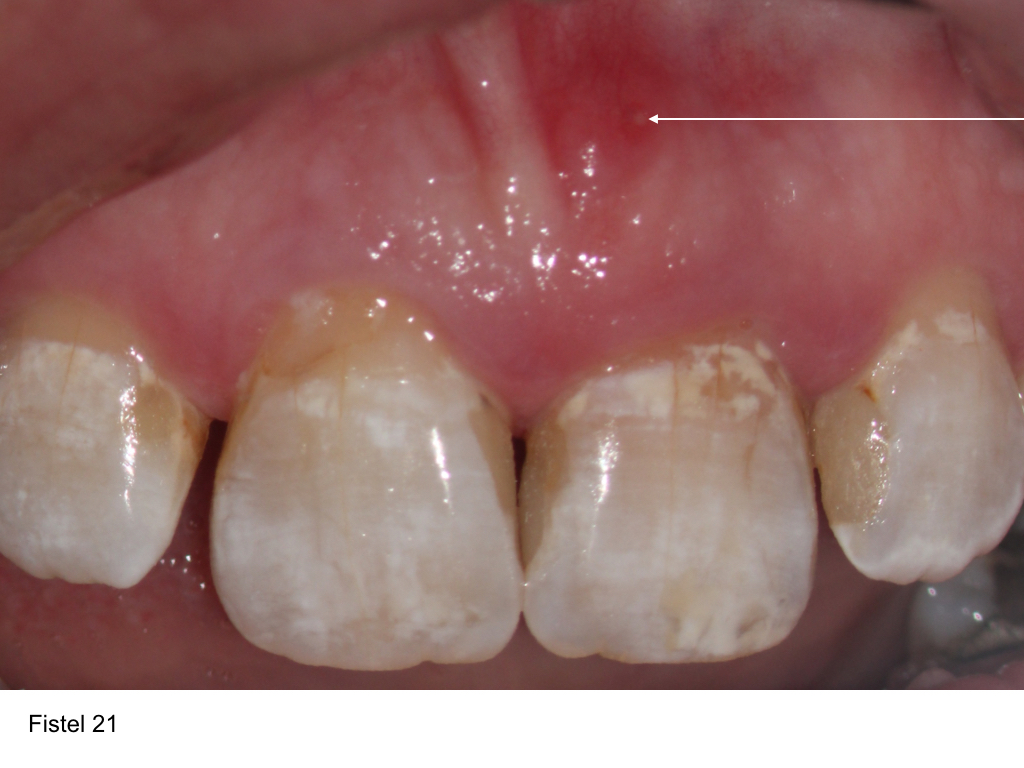

Lateraler Kanal

klinische Situation